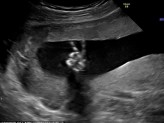

ഗര്ഭപാത്രത്തില് നിന്നൊരു വിജയചിഹ്നം!

09 March 2015

ഗര്ഭാവസ്ഥയില് സ്കാന് ചെയ്യാന് പോകുന്ന ഏതൊരു സ്ത്രീയും ഉല്കണ്ഠയിലായിരിക്കും. ഗര്ഭത്തിലുള്ള കുഞ്ഞിന് എന്തെങ്കിലും ദോഷങ്ങളുള്ളതായി സ്കാനില് കണ്ടുപിടിക്കപ്പെടുമോ എന്നൊക്കെയായിരിക്കും ചിന്ത. യു...